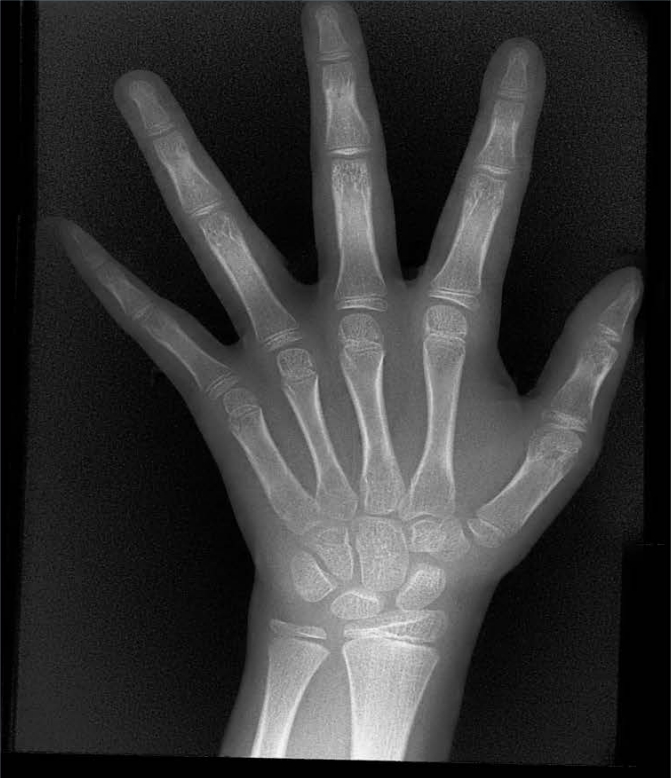

X射線(xiàn)骨齡儀通過(guò)拍攝兒童手腕部(指骨、掌骨、腕骨)的X射線(xiàn)影像,依據(jù)骨骼的形態(tài)、大小、鈣化程度等特征,結(jié)合評(píng)估標(biāo)準(zhǔn)(如《中國(guó)青少年兒童手腕骨成熟度及評(píng)價(jià)方法》,簡(jiǎn)稱(chēng)《中華-05》標(biāo)準(zhǔn))進(jìn)行骨齡判定。相較于傳統(tǒng)檢測(cè)方式,X射線(xiàn)骨齡儀具有輻射劑量低、影像清晰度高、檢測(cè)效率高的優(yōu)勢(shì),能精準(zhǔn)捕捉骨骼發(fā)育的細(xì)微變化,為骨齡評(píng)估的準(zhǔn)確性提供保障。